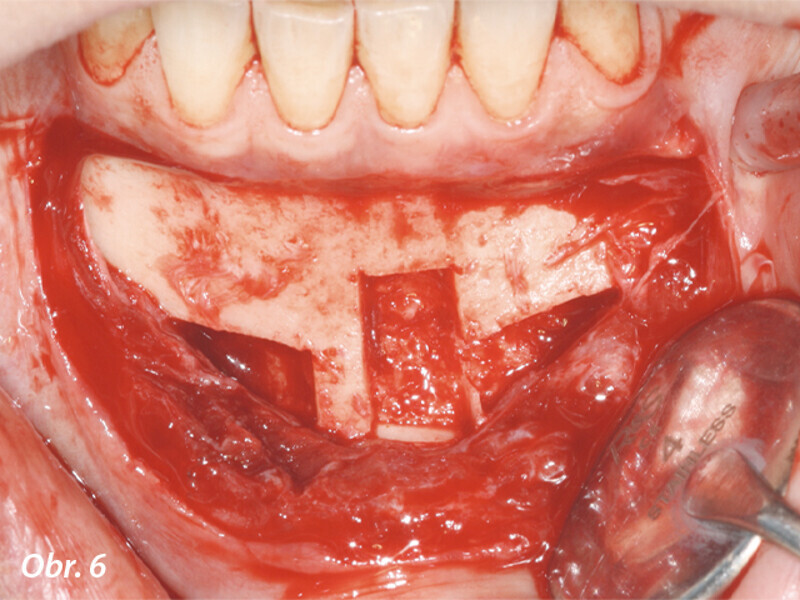

Opětovné implantologické ošetření